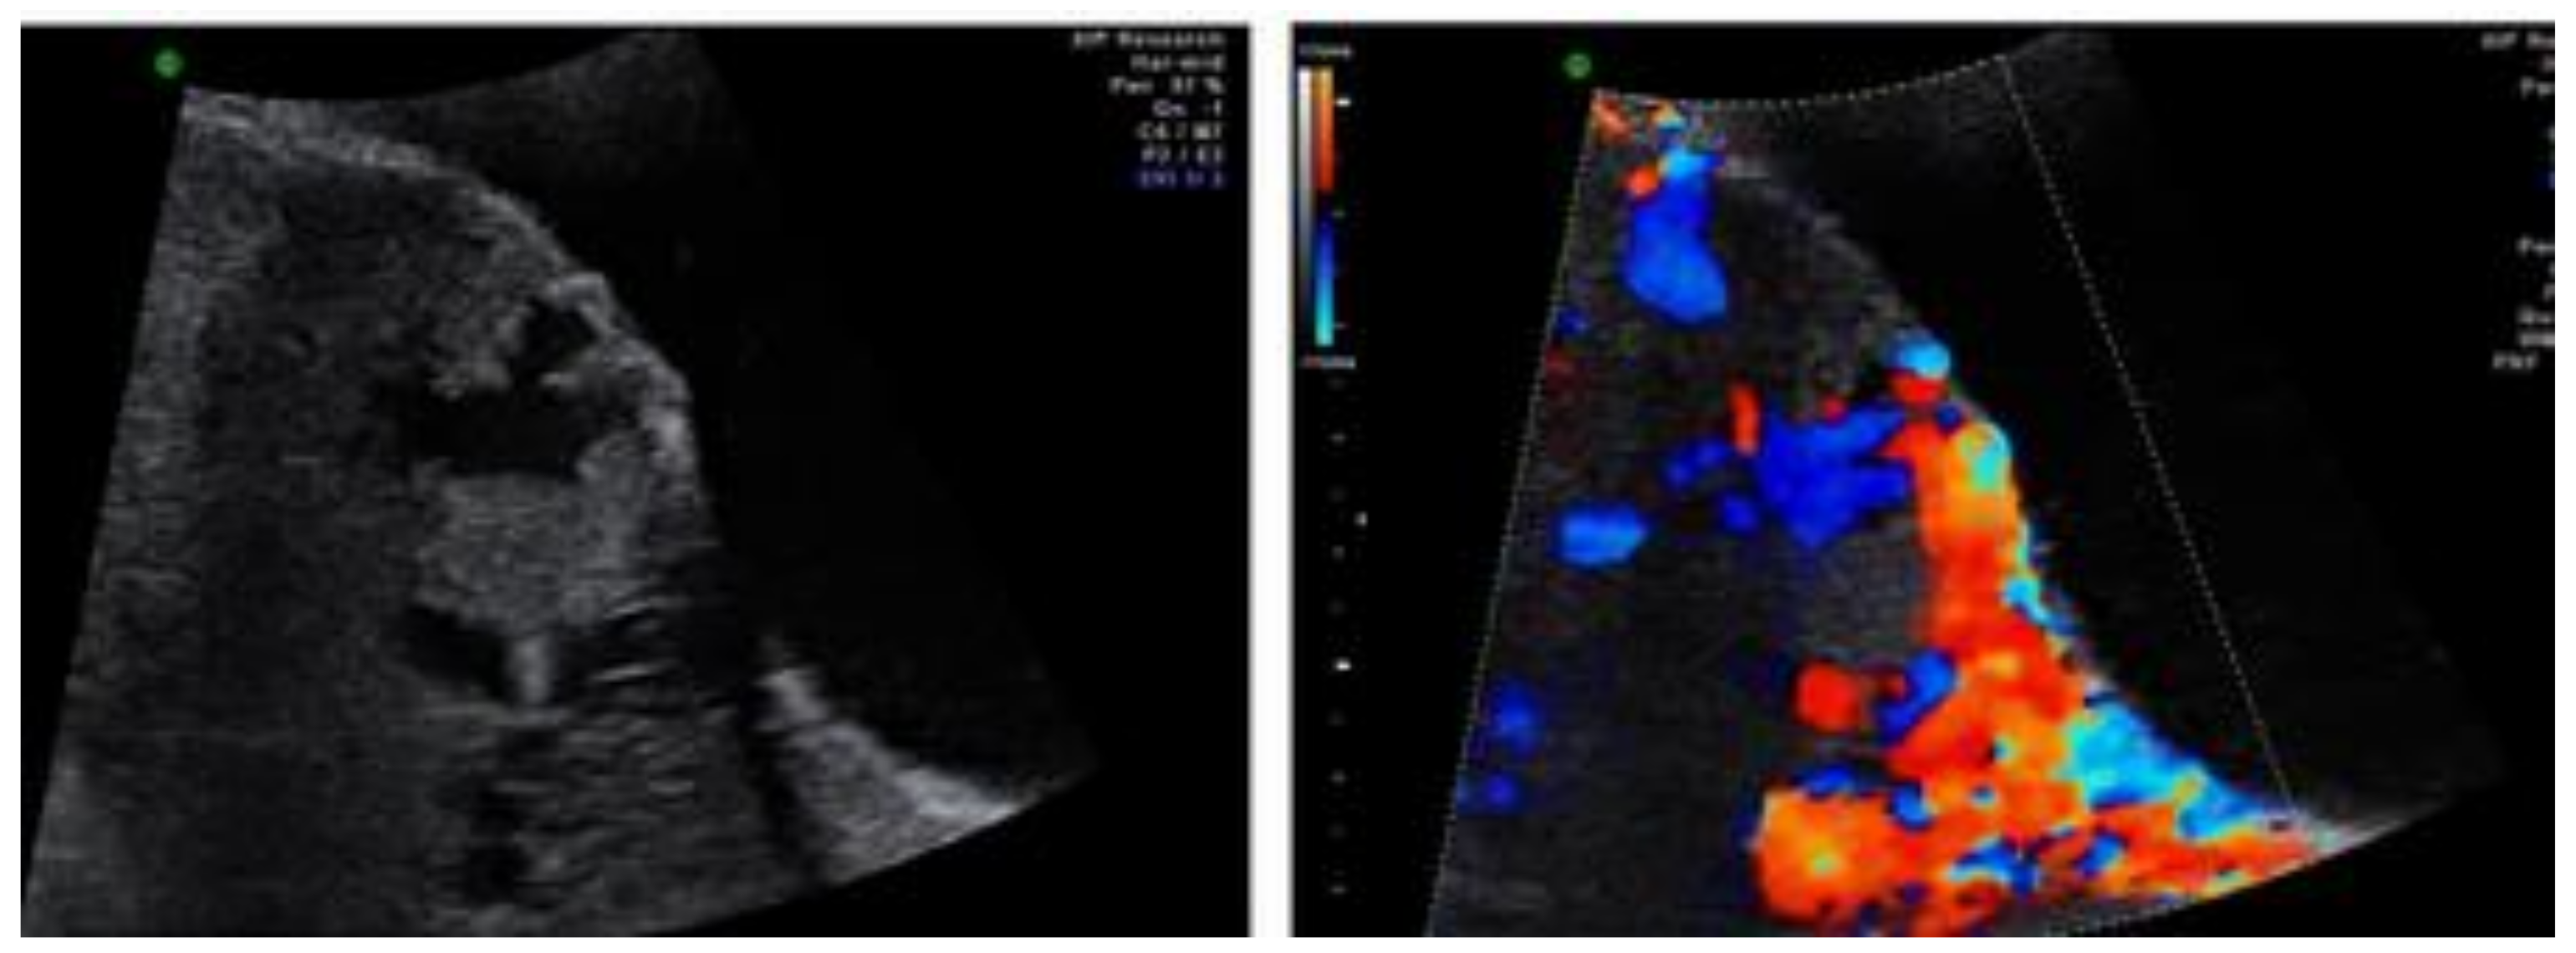

2. Case 1: History, Investigations, Treatment, and Outcomes

3. Case 2: History, Investigations, Treatment, and Outcomes

4.1. Diagnostic Comments